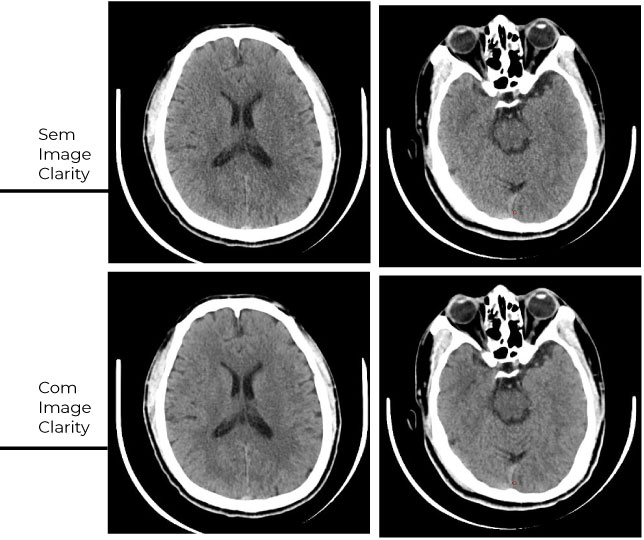

Redução de ruídos e artefatos

Imagens mais nítidas